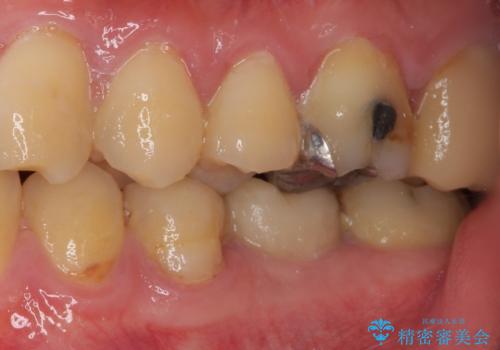

セラミッククラウンによる奥歯のむし歯治療

- 奥歯がしみて痛いとのことで来院された患者様です。

既に複数箇所の修復が行われていたため、オールセラミッククラウンにて補綴をすることとしました。

以前装着した修復物が不適であり、歯肉が腫れていましたが、仮歯を装着したことで腫れは解消されました。